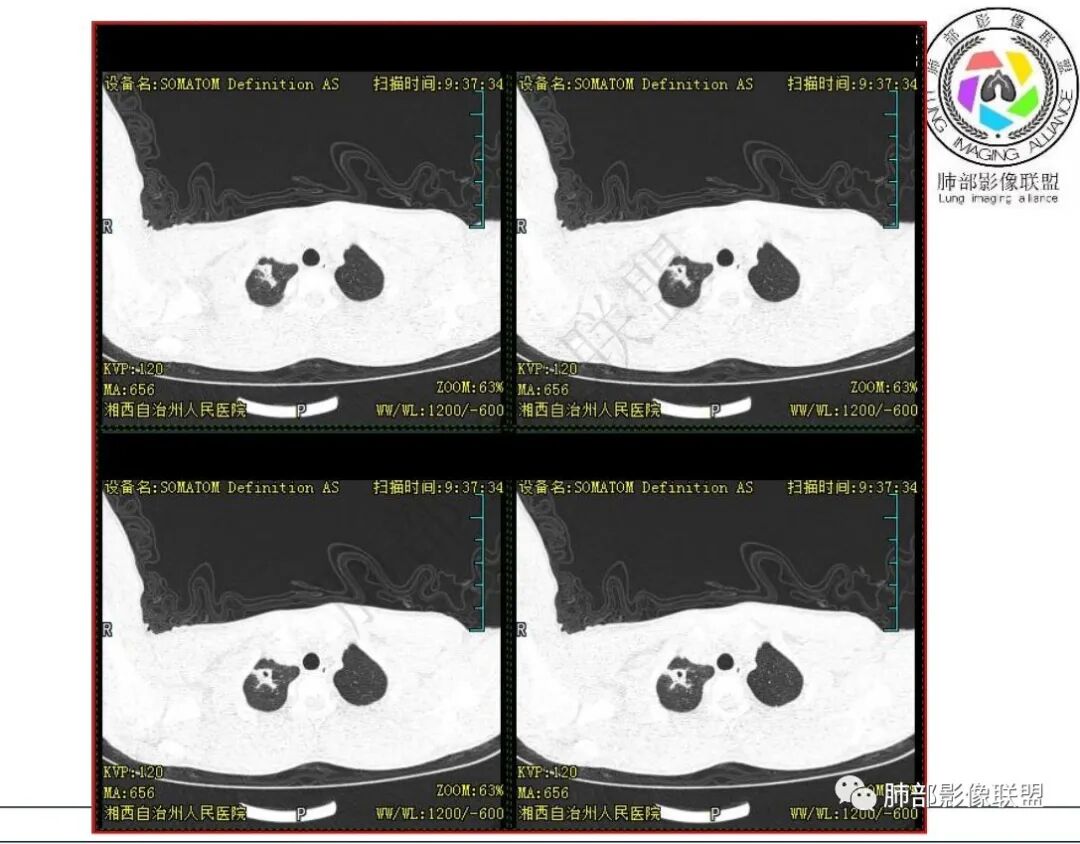

1.青少年男性,急性起病,咳嗽咳痰伴咯血盗汗10余天。既往有结核病患接触史。

2.实验室:血沉增高,淋巴细胞稍低,其他无特殊。

3.首次CT提示:右肺上叶多发结节影及实变影,簇状分布,周围散在磨玻璃影,结节内多类圆形空洞,内壁光整,有一定张力,偶见液平。部分支气管壁增厚。